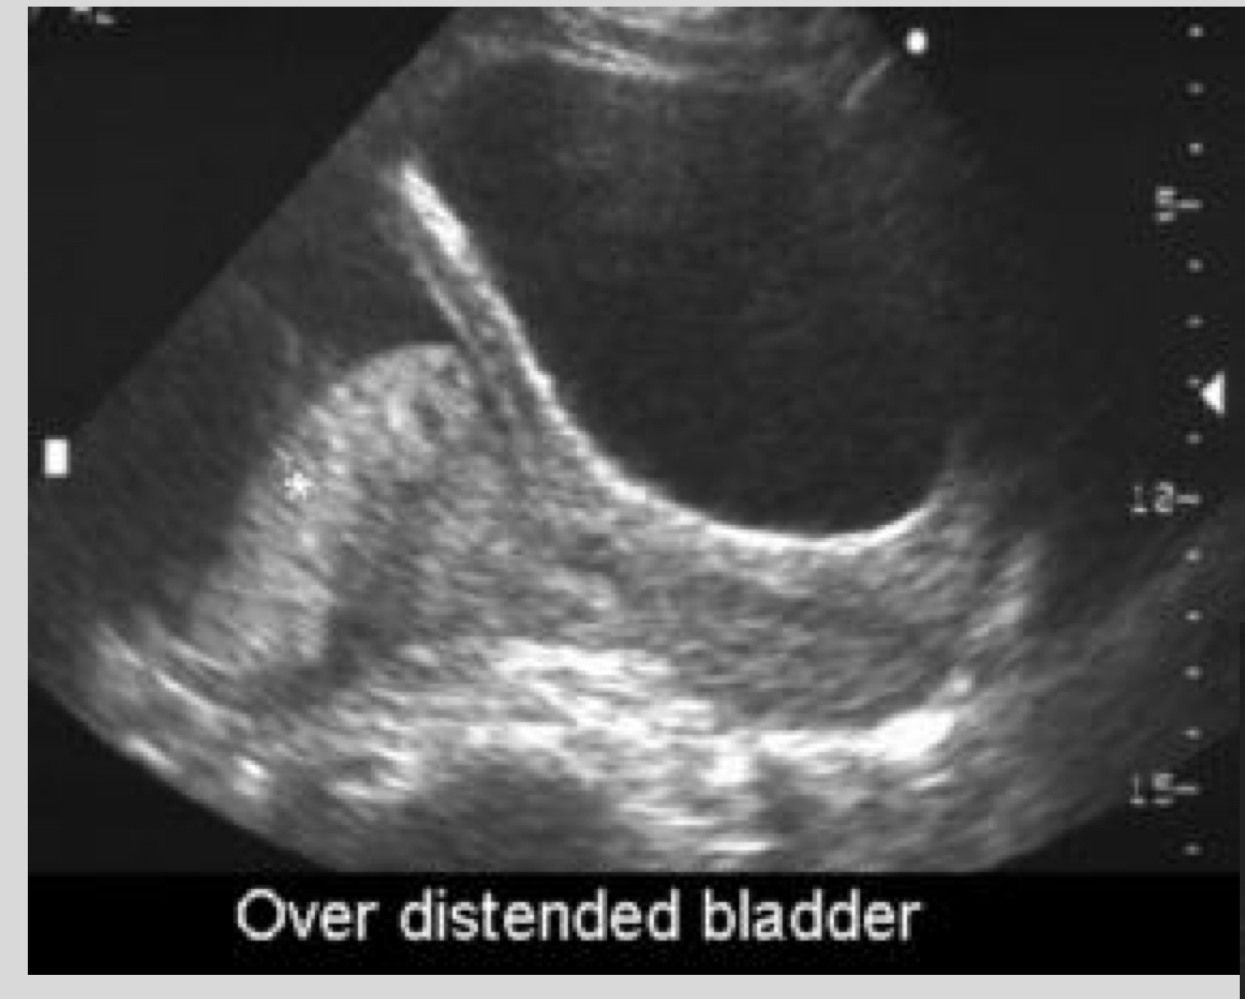

What is a false placenta previa

Apparent previa caused by lower uterine segment contraction

What should you do if a contraction mimics previa

Rescan in 10-20 minutes

What must be done before diagnosing placenta previa

Post-void scan or transvaginal ultrasound